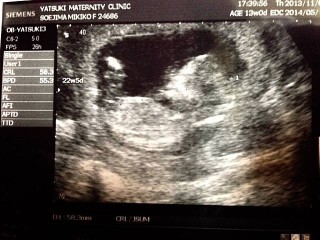

初めての経腹エコーで、6.7センチでした(^^)体をよじって元気に動いてました(^^)心音もしっかり聞こえて「うん、順調だねぇ!!」とのことでした☆

初めての妊娠で、今回の検診からお腹の上からのエコーになりました(^^) 前回まではキューピーちゃんだったのに、成長の早さにビックリです。 頭からお尻まで58.3mmでした。 検診中ずっと手足バタバタで可愛くてたまりませんでした(^^) エコー動画はDVDにしてもらってるので、今後も検診が楽しみ☆

BPD 24.5mm

CRL 58.3mm